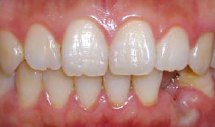

术区常规消毒铺巾,碧蓝麻阻滞加浸润麻醉,牙槽脊顶切开翻瓣,尖钻定位,逐级备洞,植入牙槽窝清创后预备植牙窝,植入种植体(Replace Select®,4.3 mm×13 mm),唇侧缺损处填充自体骨屑。拧上愈合基台,穿龈愈合,严密缝合,常嘱术后4个月后复诊取模,2周后戴牙